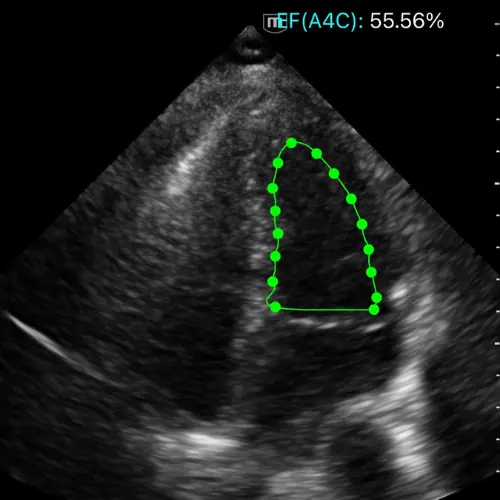

Fonction Systolique du VG

L’œil clinique comme capteur hémodynamique